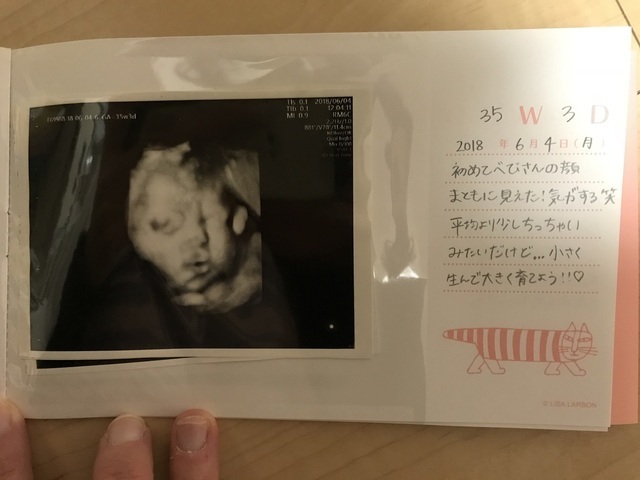

35週3日(35w3d・女の子)|ななせまん さん(26歳)

エコー写真撮影時のエピソード:

逆子だったり、胎盤に顔をくっつけていたりして、なかなか顔を見ることができなかったので、初めてまともに顔が見えた写真です。産休に入ったばかりで、時間を持て余していたので部屋中の掃除ばかりしていました。つわりはおさまり、ごはんがとても美味しく感じられるようになっていたので、1人で食べるお昼ご飯もしっかり作り、夜ごはんも時間をかけて準備して、おいしいものを食べるようにしていました。